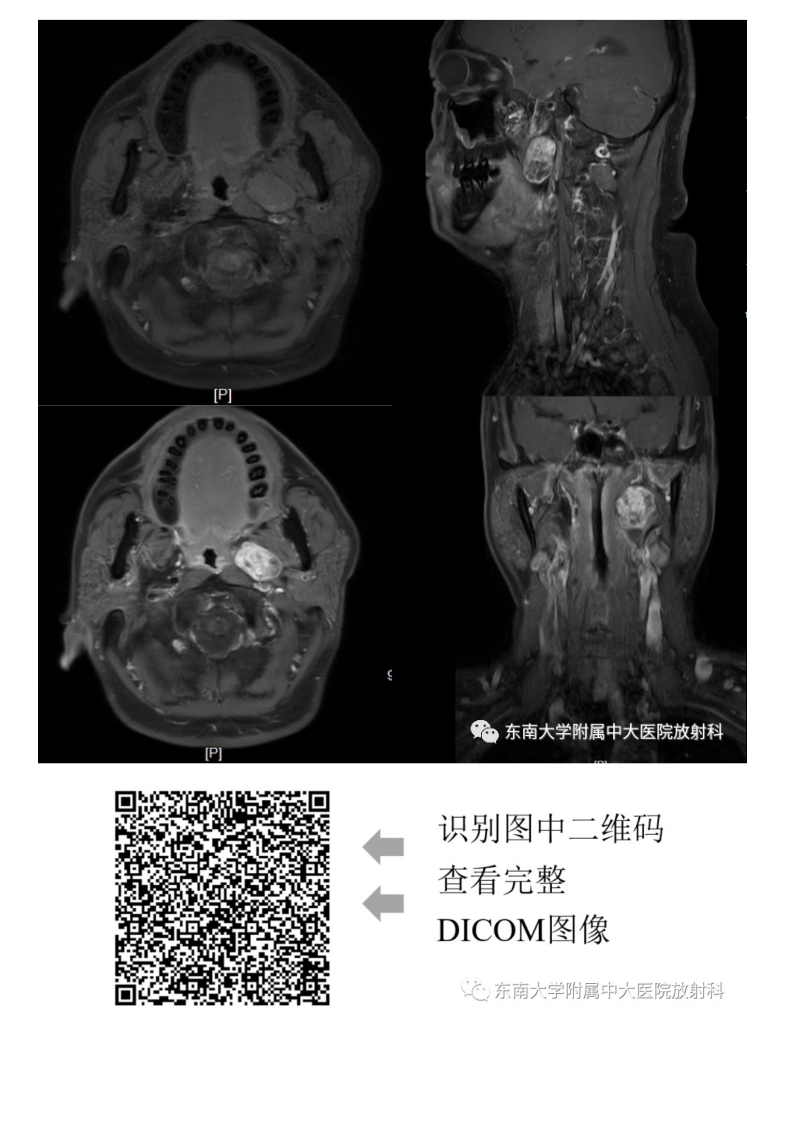

20210617_2【晨读结果公布】2021.06.17头颈部疾病——多形性腺瘤.pdf